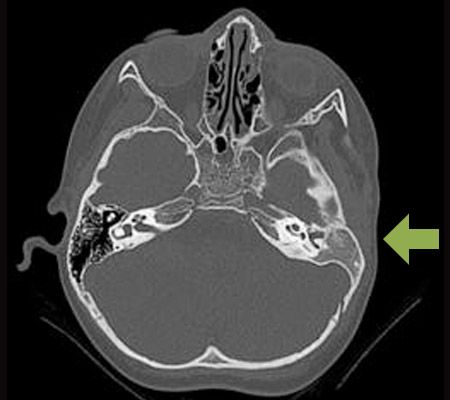

If your child suffers from aural atresia, he or she may be a candidate for ear canal reconstruction. Dr. Reinisch will take a CT scan of the inner ear to make sure that he or she has a healthy cochlea, which is necessary for successful surgery. The majority of patients at our Beverly Hills microtia surgeon's office meet this requirement. These images will also reveal whether the inner ear bones have fused together, another condition that will limit candidacy for surgical repair. Children must be at least two-and-a-half years old to receive a CT scan. Dr. Reinisch will consult with an audiologist, otologist, and other specialists to determine your child’s eligibility for treatment.